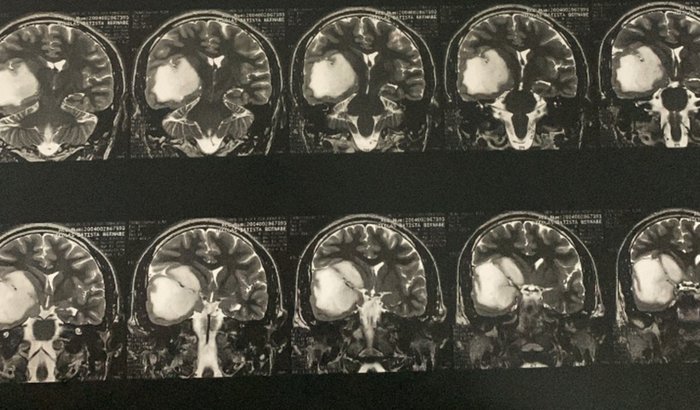

Me chamo Nikolas, tenho 24 anos, e no final de 2023 descobri um tumor cerebral com o qual venho lutando desde então. Estes tumores são expansivos e desde então tenho tido sintomas frequentes de epilepsia que, além de toda a luta, atrapalham a minha vida em todos os seus setores.